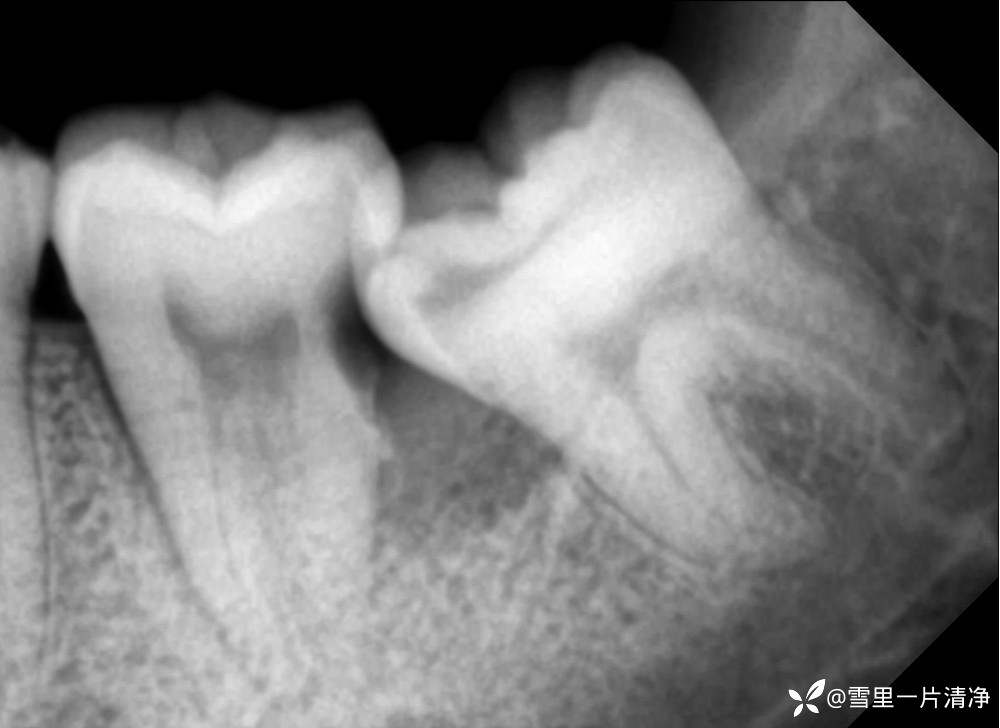

7号牙不松动,根干完整,7、8邻面有三角形骨吸收,形成清洁盲区,加上7号牙的支抗作用促进龋坏,7仅冷水入冬疼

这个方案就很自由

摆烂方案:拔7留8

挑战方案:拔完8立刻进行7先失活1周

超级摆烂方案:失活7,干髓